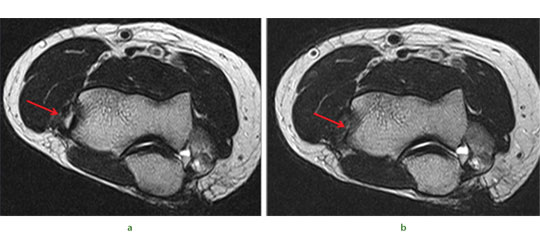

Fig. 4 Radiographs of a 51-yearold man who presented with left knee pain and instability, showing a) distraction osteogenesis and evidence of callus formation one week after injection of PBSC into corticotomy site (red arrow), and b) signifi cant growth of new bone after four months.